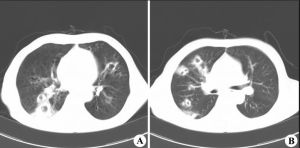

(5)深部膿腫經B超檢查可呈液性暗區。

2.深部:膿腫為局部瀰漫性腫脹,疼痛及壓痛,波動不明顯,試驗穿刺可抽出膿液,也可作超音波協診。